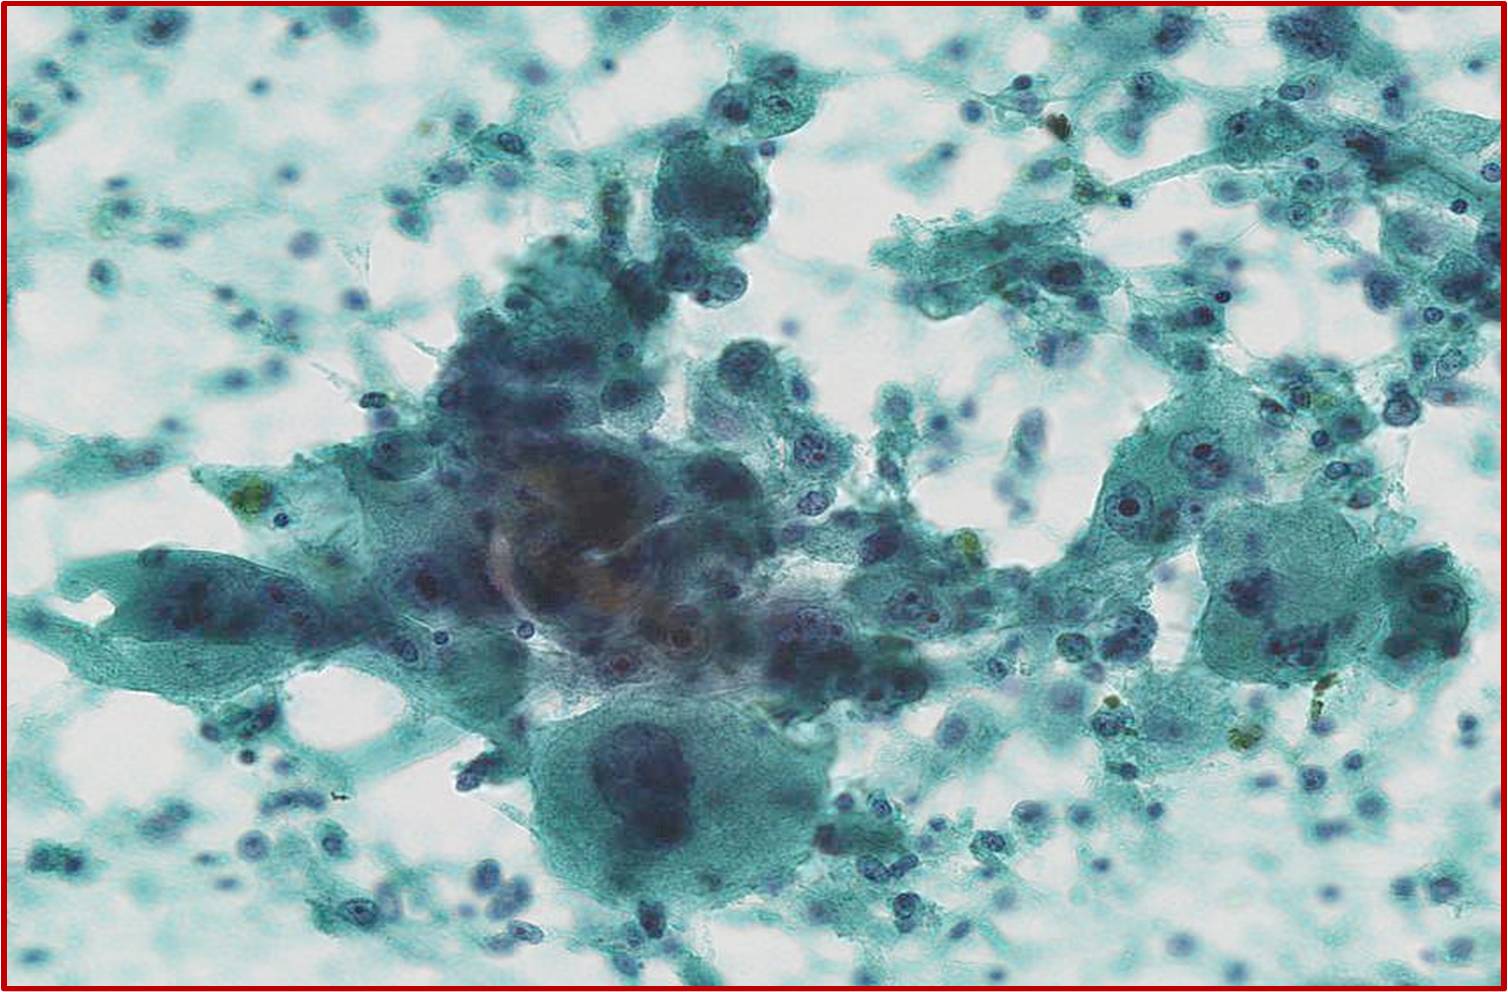

症例1

年齢,性別:40代,男性

材料/臓器:自然尿,膀胱洗浄

処理/塗抹法:沈渣すり合わせ

臨床情報:血尿

解答 選択肢 3:

高異型度の尿路上皮癌

陽性,高異型度尿路上皮癌

組織診断:

TUR 浸潤性尿路上皮癌,腺上皮への分化を伴う